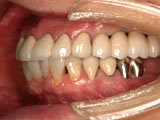

当院では1987年にITIストローマンインプラントによる部分欠損への応用、 また1989年にブローネマルクインプラント用いた無歯顎インプラント治療 (歯がすべてなくなった人へのインプラント治療)を開始しました。

昨今、人体の再生医療の進歩には目を見張るものがあります。それに伴い骨の再生の研究が進み、インプラント治療も進化しつづけております。1980年代以後、現在に至るまで世界中でいろいろなインプラントが開発されております。その中から当院では現在ブローネマルクインプラント、ライフコアーインプラント、 スプラインインプラント、GCインプラントなどのインプラントを使用しております。

インプラント治療にはいろいろなご意見があります。歯がなくなった方、すべての患者様においてインプラント治療が一番良いというわけではありません。正しい診査診断により決定すべきです。しかし、インプラント治療が歯科医学的に良いとか悪いとかと言う議論をする時代ではなくなりました。 インプラント治療は歯の欠損修復治療として確立されたと言えるでしょう。